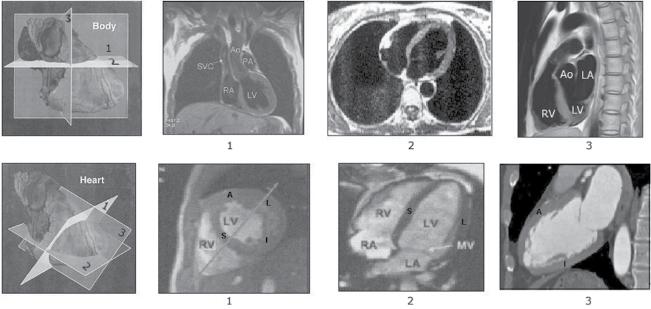

Figure 1.3 Examples of exercise test – nuclear imaging (SPECT) correlation. (a) Above: Observe the three heart planes with their transections (see Figure 1.4b) used by nuclear medicine experts (and other imaging techniques) to transect the heart: (1) short‐axis (transverse) view (SA), (2) vertical long‐axis view (VLA) (oblique sagittal‐like), and (3) horizontal long‐axis (HLA) view. The short‐axis transections are at the mid‐apical level (see Figure 1.8). The segmentation of the heart used in this book is shown (Cerqueira, Weissman, and Disizian 2002). In the middle is also a bull’s eye image presented. This patient has normal left ventricular perfusion. (B) Above: In the three planes (SA, VLA, and HLA): (A) normal uptake at rest (Re) and during exercise (Ex) can be observed. Middle: Abnormal uptake only during exercise of segments 7, 13, and 17 (see Figure 1.8) in a patient with ischemia produced by distal involvement of a non‐wrapping LAD. The basal part of the anterior wall of the LV is not involved. Below: abnormal uptake during rest and exercise in a patient in the chronic post‐MI phase caused by distal occlusion of very long LAD that wraps the apex involving part of the inferior wall (segments 7, 13, and 17 and also 15) (see Figure 1.8). In this case abnormal uptake is also evident in the rest image (see plate 3 in color plates).

Figure 1.4 CMR imaging. (a) Transections of the heart following the classical human body planes: (1) frontal plane, (2) horizontal plane, and (3) sagittal plane. (b) Transections of the heart following the heart planes that cut the body obliquely. These are the planes used by the cardiac imaging experts: (1) short‐axis (transverse) view, in this case at mid‐level (see b (1)); (2) horizontal long‐axis view; (3) vertical long‐axis view (oblique sagittal‐like). Check the great difference between the sagittal plane according to human body planes (a (3)) and the heart planes (b (3)). (b) shows the four walls of the heart with the classical names: septal (S), anterior (A), lateral (L) and inferoposterior. Currently, the inferoposterior wall is for consistency named inferior (I) (see Figure 1.8).